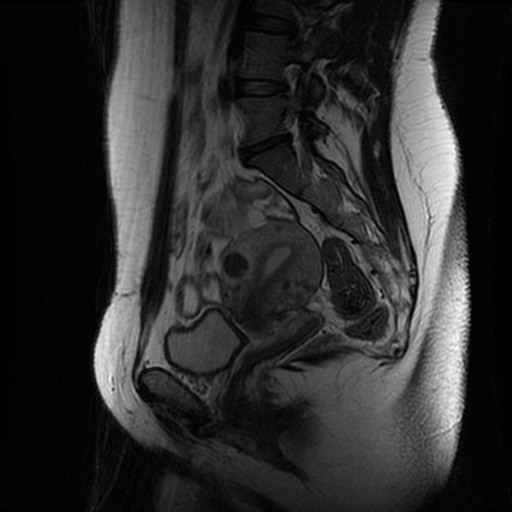

LWZ